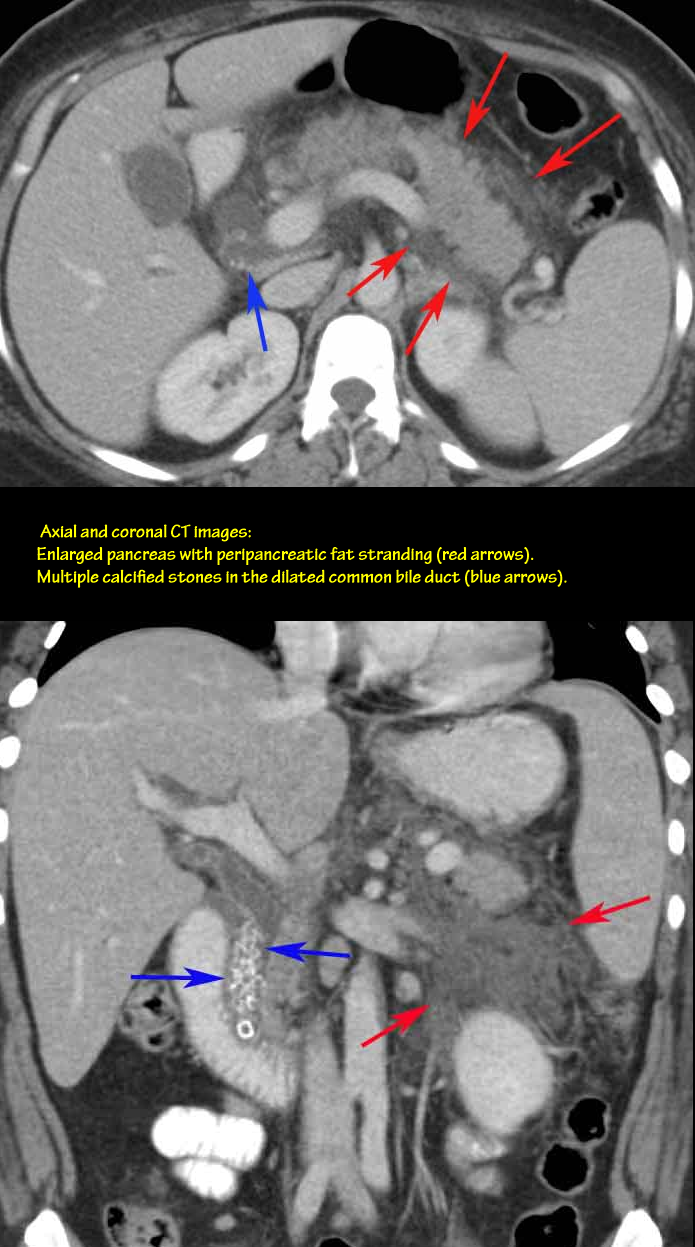

44yo obese female with severe upper abdominal pain.

Cholelithiasis

• extra-hepatic obstructive jaundice

• also had gallstone pancreatits

• at risk for ascending cholangitis